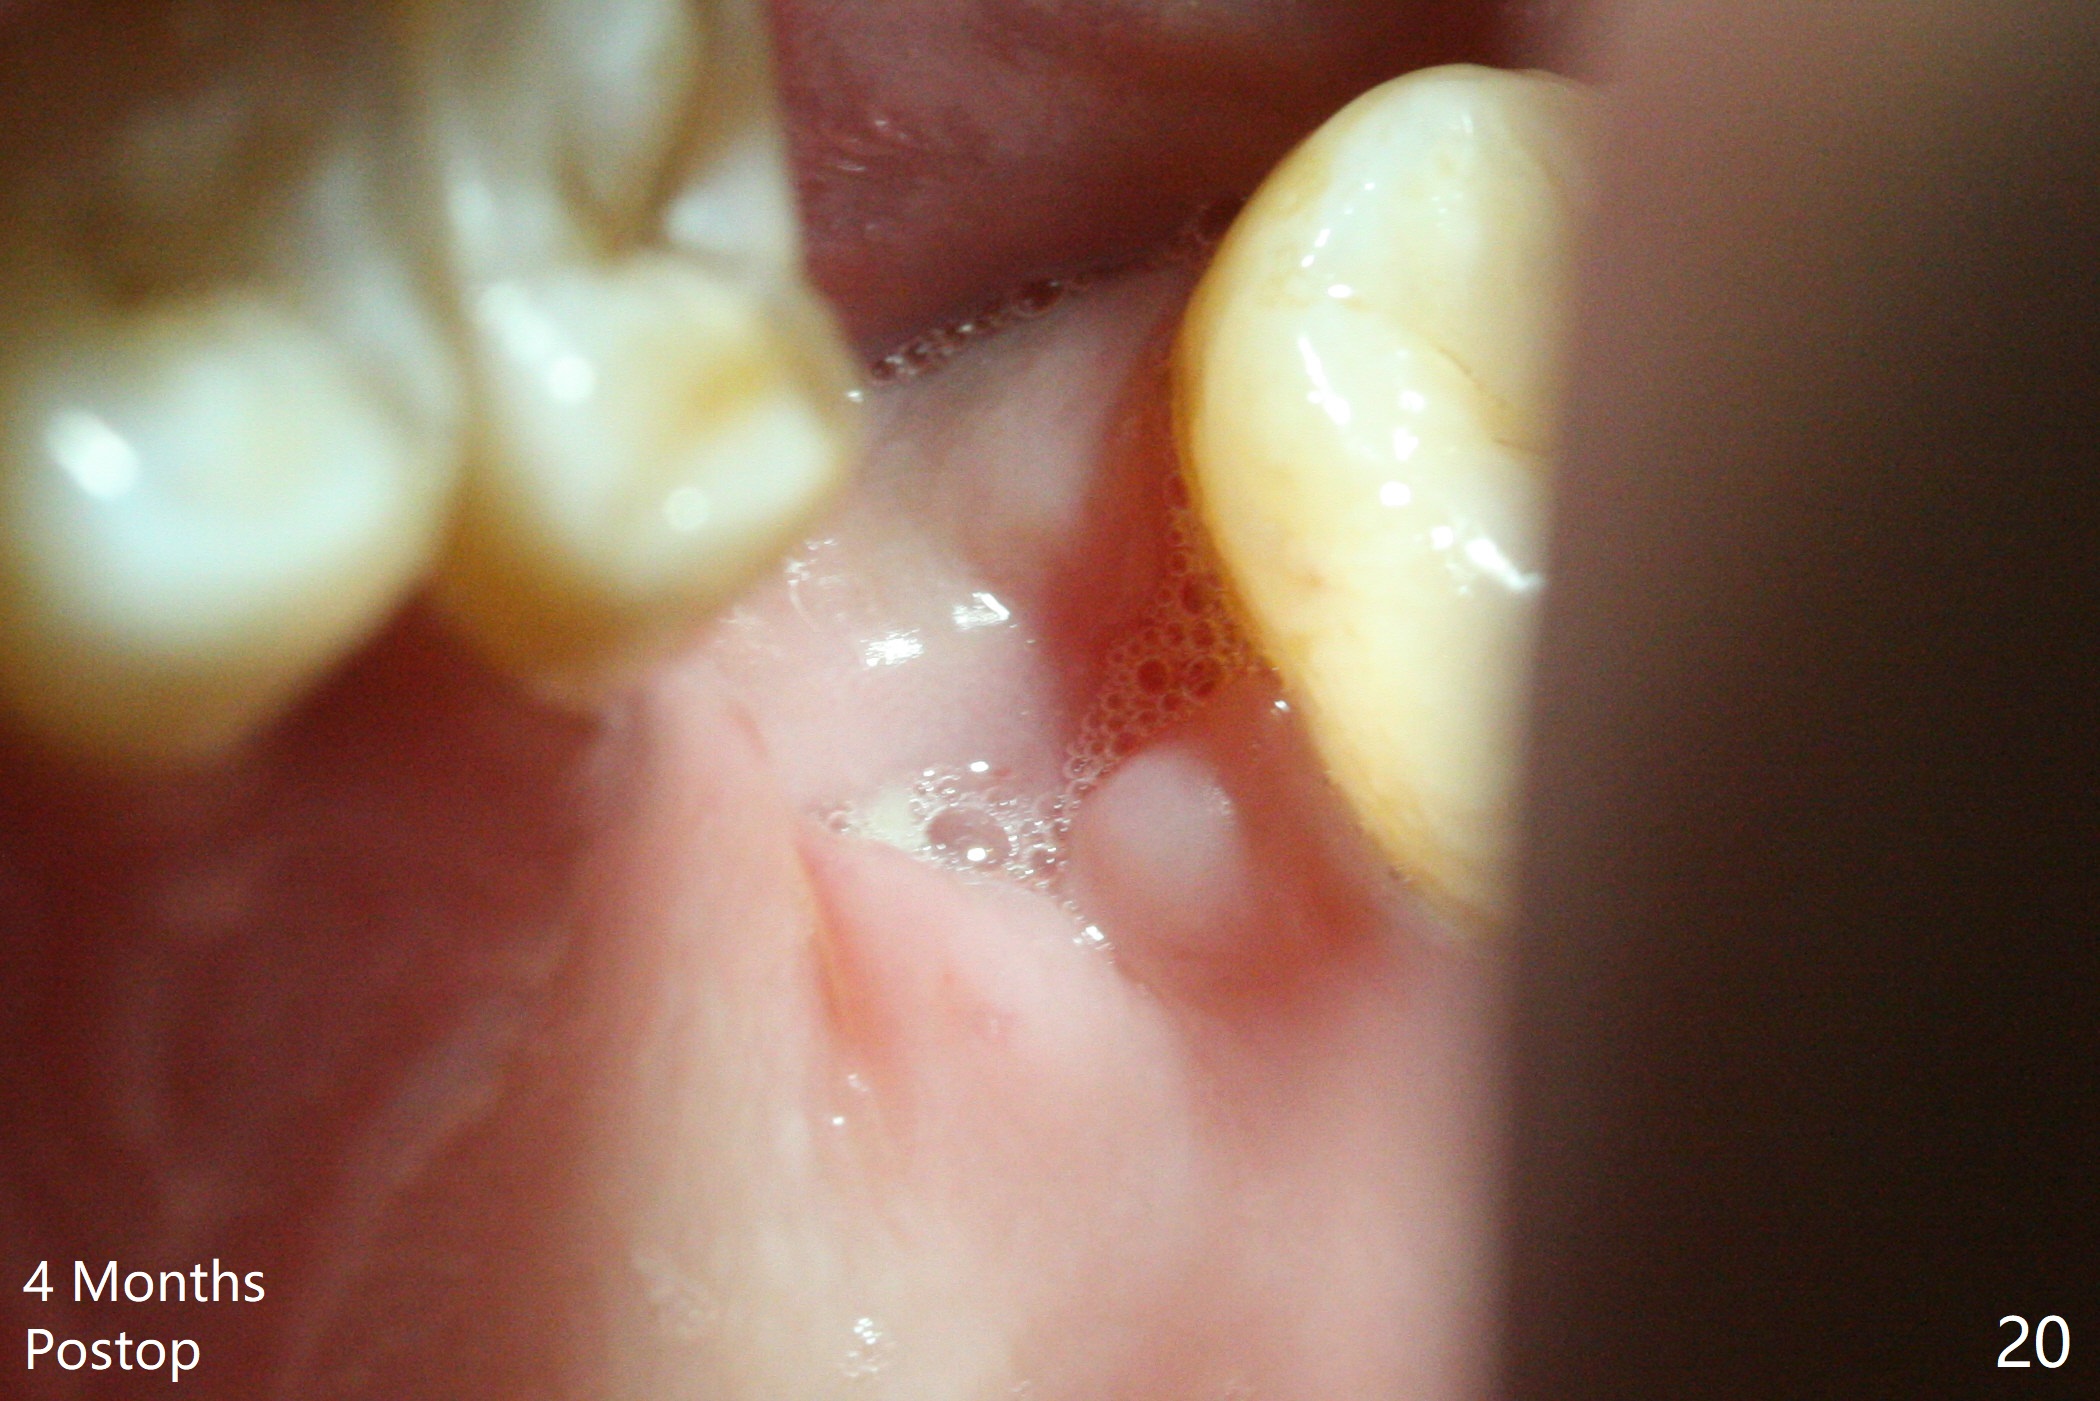

Poor visibility for immediate implant in the molar region is another contributing factor for the dislodgement.  The patient returns for follow up 15 days (Fig.15) and 1 month (Fig.16) postop.  Bone graft seems to be stable around the implant.  The socket heals 4 months postop (Fig.20).  The implant seems to have been osteointegrated (Fig.17,18).  It will be backed up for ~ 3 mm to improve implant/crown ratio (Fig.19, as compared to Fig.14).  If it cannot be done, take impression immediately and make a subgingival provisional before suturing.

In fact, there is no coronal bone for the implant to be backed up.  Therefore, impression is taken after uncover and insertion of a 5.5x5.7(4) mm abutment.

There is a mushroom around the implant nearly 5 months postop/immediately before cementation (Fig.21).  The bone density around the implant is low (Fig.22-24' *).